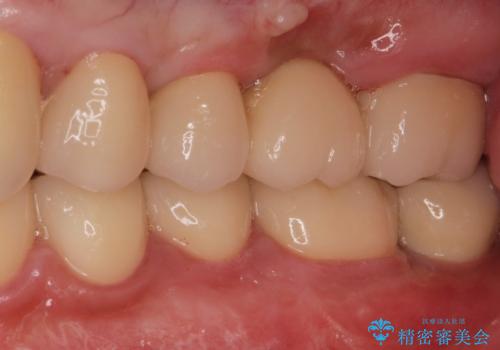

適合の良い被せ物、インプラントが入りました。

全ての治療が終わった後はNG(ナイトガード)を使用し、定期的にメンテナンスに

くることをお勧めしたいます。